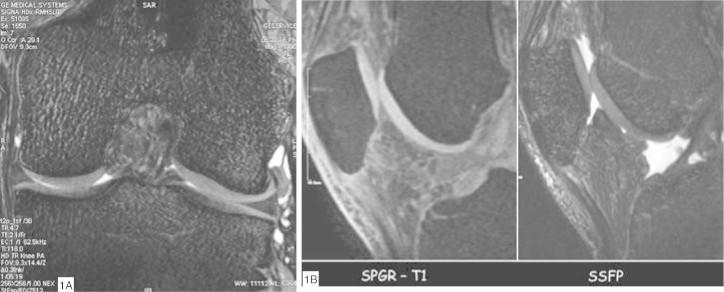

Through the ability of magnetic resonance imaging (MRI) to characterize soft tissue noninvasively, it has become an excellent method for evaluating cartilage. The development of new and faster methods allowed increased resolution and contrast in evaluating chondral structure, with greater diagnostic accuracy. In addition, physiological techniques for cartilage assessment that can detect early changes before the appearance of cracks and erosion have been developed. In this updating article, the various techniques for chondral assessment using knee MRI will be discussed and demonstrated.